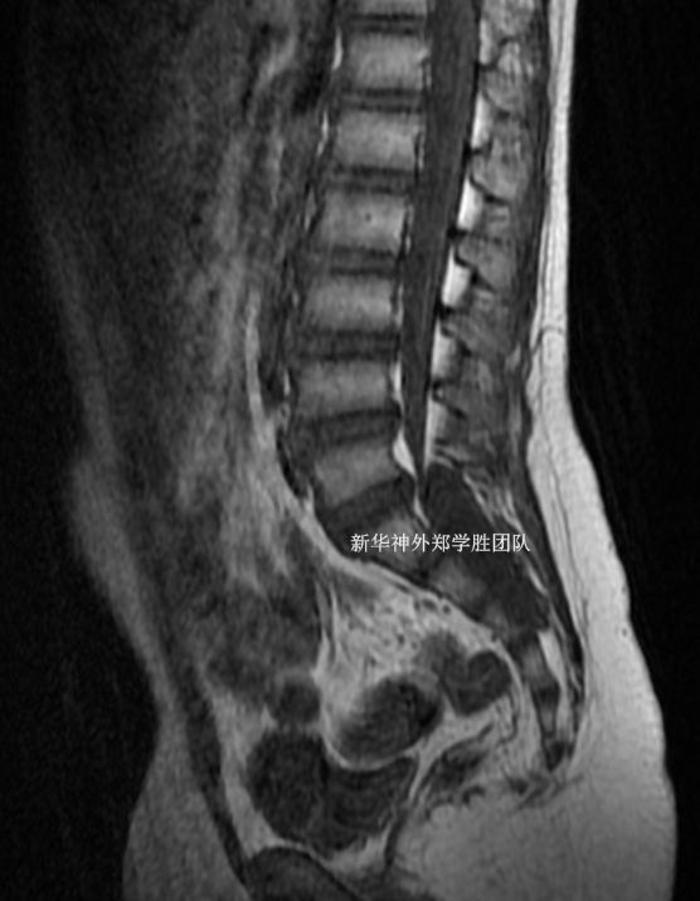

十岁儿童,因为经常腰痛、有时大便困难,检查磁共振发现巨大骶管囊肿,从腰5下缘延伸到骶4上缘。

CT检查还发现严重的脊柱裂,整个骶管全部裂开。

手术中非常顺利,完全封堵了骶管囊肿,并且修补了脊柱裂。由于患儿本身的脊柱裂和骶管囊肿对骨质的侵蚀,骶骨骨质缺损很严重,所以我们手术中没有切除任何骨质,完全是利用了疾病本身形成的骨质缺损区完成了手术。通过钛板修补,术后骨质比术前更完整了。